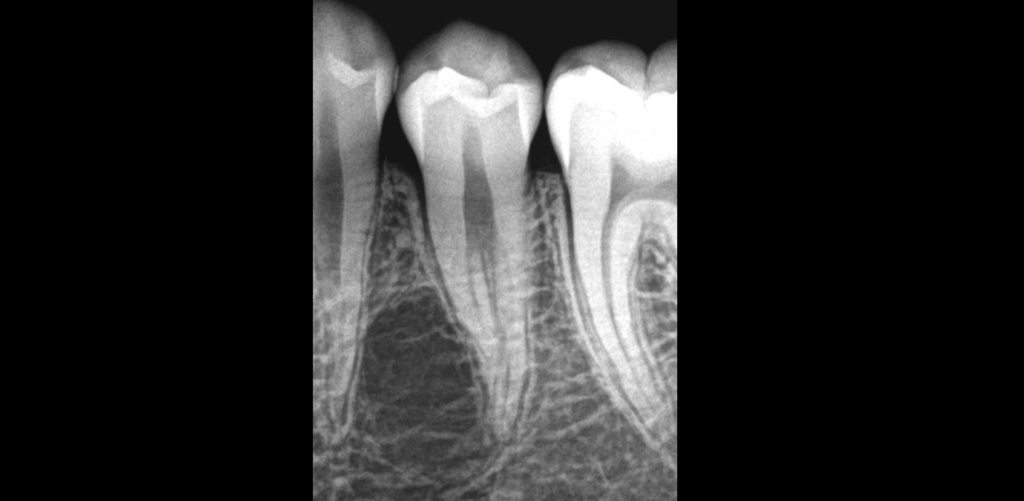

🦷 Patiente adressée pour un traitement canalaire, en raison d’une 𝐢𝐦𝐚𝐠𝐞 𝐫𝐚𝐝𝐢𝐨𝐜𝐥𝐚𝐢𝐫𝐞 𝐥𝐚𝐭𝐞́𝐫𝐨-𝐫𝐚𝐝𝐢𝐜𝐮𝐥𝐚𝐢𝐫𝐞.

🔎 L’anatomie a l’air sympa… ça promet d’être un bon challenge ! 😃

📍 Mais le test de sensibilité pulpaire est normal.

✅ 𝐂𝐞𝐭𝐭𝐞 𝐩𝐮𝐥𝐩𝐞 𝐯𝐚 𝐦𝐚𝐠𝐧𝐢𝐟𝐢𝐪𝐮𝐞𝐦𝐞𝐧𝐭 𝐛𝐢𝐞𝐧, nous n’avons pas de raison de la traiter.

🔬 Il s’agit d’une 𝐥𝐞́𝐬𝐢𝐨𝐧 𝐨𝐬𝐬𝐞𝐮𝐬𝐞 𝐝’𝐨𝐫𝐢𝐠𝐢𝐧𝐞 𝐧𝐨𝐧 𝐞𝐧𝐝𝐨𝐝𝐨𝐧𝐭𝐢𝐪𝐮𝐞 : ici, un 𝐤𝐲𝐬𝐭𝐞 𝐨𝐬𝐬𝐞𝐮𝐱 𝐬𝐨𝐥𝐢𝐭𝐚𝐢𝐫𝐞 (la lacune était vide et sans membrane).